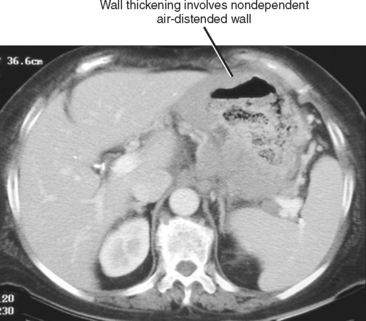

Gastric cardia radiology. Diagnostic centers of america dca is a leading diagnostic imaging facility offering a full array of imaging services in palm beach county florida. We have five state of the art radiology imaging centers in boca raton boynton beach delray beach and wellington florida. The gastric cardia is characterized on barium stud ies by three or four stellate folds that radiate to a central point at the gastro esophageal junction also known as the cardiac rosette fig 2 12. Variations and benign influences may closely resemble the more dangerous lesion.

Thick tortuous folds or lobulated filling defects in the cardia or fundus. Right gastroepiploic artery inferiorly and left gastroepiploic artery and short gastric arteries superiorly fundus of the stomach. Results of surgical treatment of carcinoma of the esophagus and gastric cardia. The collection of cases presented here comprises only that material which is rare in our experience or quite new to us.